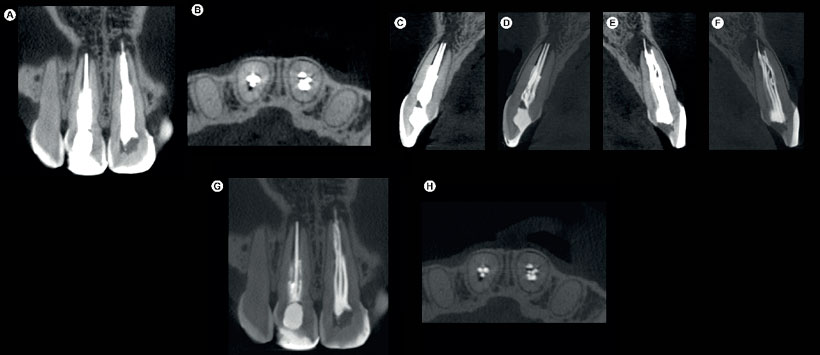

Figura 1: (A-B) El informe de CBCT producido por e-Vol DX muestra los dientes # 11 y 21 con artefactos de contraste blancos, lo que dificulta la identificación del tratamiento fallido del conducto radicular; (C-H) en las imágenes de e-Vol DX CBCT, se usó el filtro y se conservó el contraste de la escala de grises, lo que reduce las áreas blancas de la imagen original.